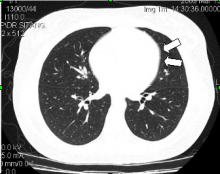

On examination she was look well. Her pulse rate was 92 beats/min, blood pressure was 100/67 mmHg, respiratory rate was 20 breaths/min, and oxygen saturation was  99 % on room air. Chest examination was normal, no subcutaneous emphysema and normal heart sound. A 12-lead electrocardiogram showed normal sinus rhythm. Chest X-ray demonstrated a pneumopericardium (Fig. 1) which was confirmed by computed tomography (Fig 2). The routing laboratory tests were also unremarkable. There was no evidence of other abnormalities. Gastrografin swallow show no leak or any other abnormality (Fig. 3)

Fig 2: Computed tomography reveals minimal amount of pneumopericardium (arrows).